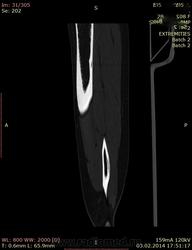

КТ голени

Здравствуйте коллеги.Поздравляю с открытием зимний олимпиады Сочи.Мне нужна ваша помощь.Девочка 1998 г, беспокоять боль, небольшая припухлостб н\3 левой голени.В сентября  в автобусе получила травму,автобус резко остановилься , левой голень придавила дверь автобуса и несколько человек упали на нее.К врачу не обрщалось, т.к. студент некогда была.Приехала на каникулы , обратилось  к нам, выше указанными жалобами.Что вы скажите, ваше мнение.Консульторовали ортопедом они сказали нужна операция и лучевая терапия.Другой онколог сказал  гной.Анализы спокойно.Родители медики, не знает что делать.Пожалуйста помогите.

Асель, картинки мелкие. Очень. По показанному подумала бы на остеоид-остеому, уточнила бы характер болей и купируется ли аспирином.

патология по типу 1а, края четкие склерозированные,распологается частично эксцентрично интрамедуллярно и большей своей частью кортикально,внутренняя структура напоминает картину битого стекла .дифференциальный диагноз -внутрикостная липома,неоссифицирующая фиброма фиброзный  кортикальный деффект,остеоид -остеома,  кортикальная фиброзная дисплазия ,организовавшаяся гематома ,абсцесс броди (хотя он чаще встречается в эпифизе).  динамическое наблюдение рекомендуется

3)для остеод-остеомы характерны преимущественно  ночные боли,купируемые НПВС.по снимкам не видно гнезда и зоны перифокального склероза,но ее не исключаю.очень мало анамнестических данных.